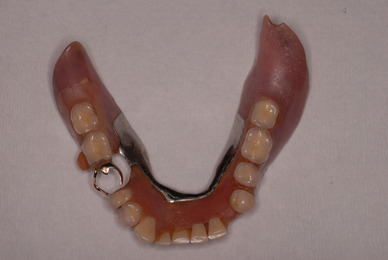

お口の中から差し歯、入れ歯、詰め物を追放しましょう!

二度とお口の中へ変なものを入れなくても済むように

「川崎市の入れ歯なら新丸子西口歯科医院へ」